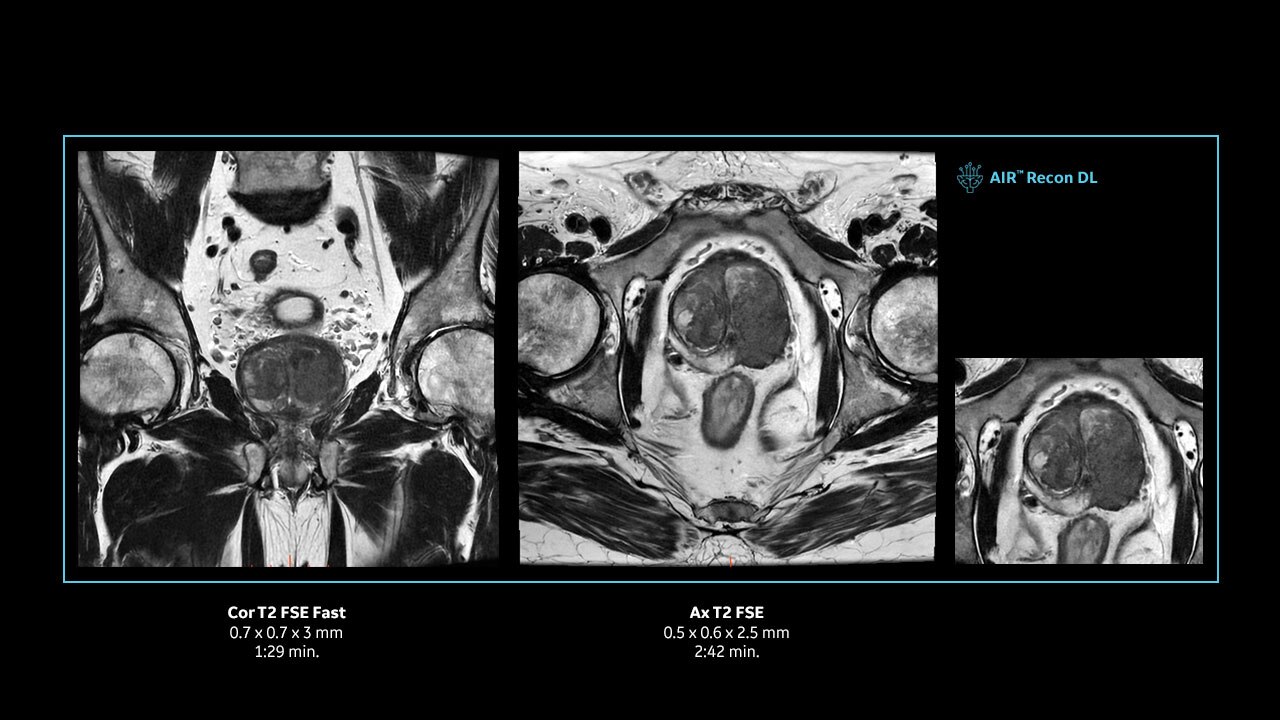

Achieve pin-sharp image quality with pioneering AIR™ Recon DL AI technology

With access to the latest advanced AI technology, you can scan all anatomies and achieve pin-sharp images. Our pioneering Deep Learning-based reconstruction algorithm AIR™ Recon DL accelerates scan time and puts patients at ease.